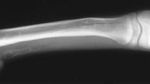

Sebuah studi mengungkapkan ada tiga pasien di Hong Kong yang mengidap kondisi langka fibular hemimelia tipe II. Ini merupakan masalah kesehatan bawaan ketika tulang betis tidak terbentuk sempurna, yang bisa membuat salah satu kaki lebih pendek dari yang lain. (Foto: The Journal of Bone & Joint Surgery)

Untuk memperbaiki panjang dan bentuk kaki, dokter menggunakan teknik Ilizarov, dengan alat cincin logam yang perlahan menarik tulang agar tumbuh memanjang. Pemanjangan dilakukan sedikit demi sedikit setiap hari, hingga terbentuk tulang baru di antara celah pemisahan. (Foto: The Journal of Bone & Joint Surgery)